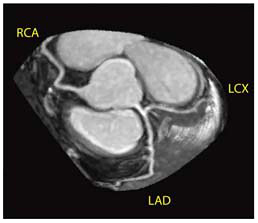

新しい心臓用Volumeアプリケーションである3D Heartでは,心筋信号を抑えるT2-prepパルスが追加されたほか,ペンシルビームを応用した新しい横隔膜同期やスライストラッキング等,さまざまな技術が搭載され,より精度の高い安定した冠動脈描出が可能となっている(図3,4,5)。また,心臓全体をマルチスラブ(5スラブ程度)で撮像することが可能となり,末梢血管の描出能も大きく向上している。

当院で3D Heartを使用したMRCAの成績は,トータル検査時間が平均20分,成功率が85%となっている。血管の描出に関しては右冠動脈,左前下行枝は,ほぼ全例で末梢まで描出され,従来評価困難であった左回旋枝でも,近位部で約9割,中間部,末梢血管でも約8割の描出が可能となっている。末梢の冠動脈病変の診断能が上がっており,今後,MRCAの使用頻度はさらに増えていくものと思われる。

図4 図3と同一症例のcurved MPR像 |